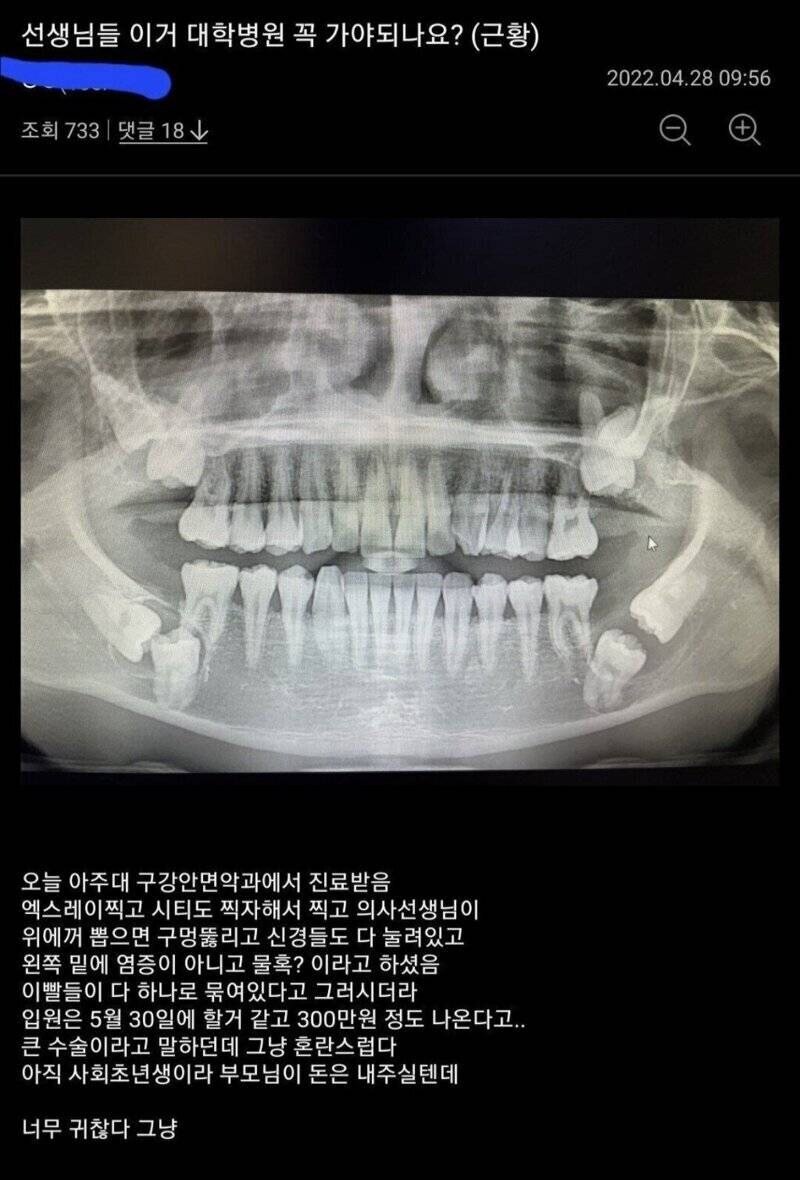

이렇게 생긴 사랑니 난생 처음 봄 ㄷㄷㄷ

처음봤을땐 사랑니 영혼 탈출 하는줄;;;;;